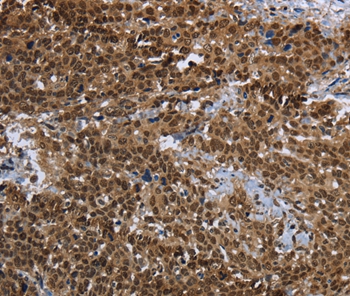

Immunohistochemical analysis of paraffin-embedded Human cervical cancer tissue using #37691 at dilution 1/25.